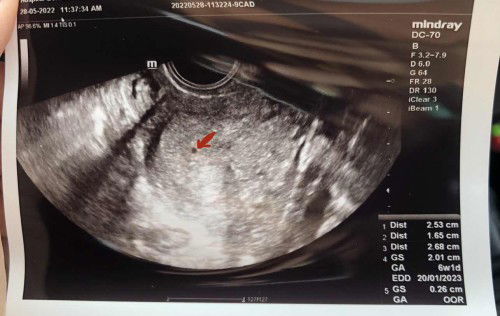

size kandungan kecik

hi momies. normal ke kandungan size mcm bentuk dot ni ? ikut kiraan masani 5weeks. doc bgthu sepatutnya 5mggu size dah besar sikit, tapi doc ckp takut salah kira & suruh dtg balik lepas 2mggu. risau pula saya. act seminggu sebelum pergi scan, saya test upt (sebab dah delay period 7hari) result upt samar2. harap momies2 dpt bagi komen2 positif #pleasehelp #firstbaby